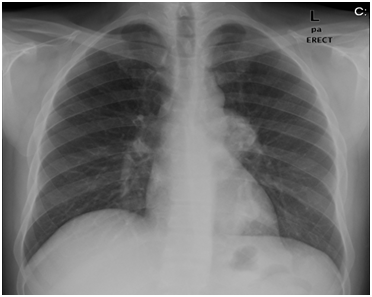

After 5-7days, his local sinonasal symptoms improved but he was as sick as before. Besides persistent headache, he started to have progressive cough and remittent fever. He was also having occasional hemoptysis. The pulmonologists were consulted and they changed the antibiotic and advised tuberculin test, sputum analysis and culture for AFB all of which were negative. They also advised chest CT that showed left lower lung lobe cavitation (Figure 2). More biopsies were taken from the nose and sinuses under general anesthesia and the pulmonologists also did fiber-optic bronchoscopy as per prior arrangement under the same anesthesia, and it was seen that the tracheobronchial tree was congested. However, they did not take any biopsy. There was strong suspicion of pulmonary tuberculosis and anti-tuberculosis therapy was commenced. The biopsy from the nose and sinuses showed non-caseating granuloma but still there was no specific diagnosis.

Figure 2 Left lung lobe cavitation.